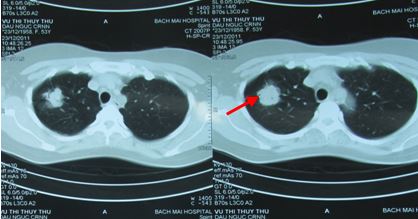

- Chụp CT scanner lồng ngực:

Hình 1: Hình ảnh chụp CT phổi trước điều trị: u phổi P kích thước 3,4cm

Hình 6: U phổi trước ĐT

Hình 7: U phổi sau ĐT 16 tháng, tổn thương xơ hóa nhỏ